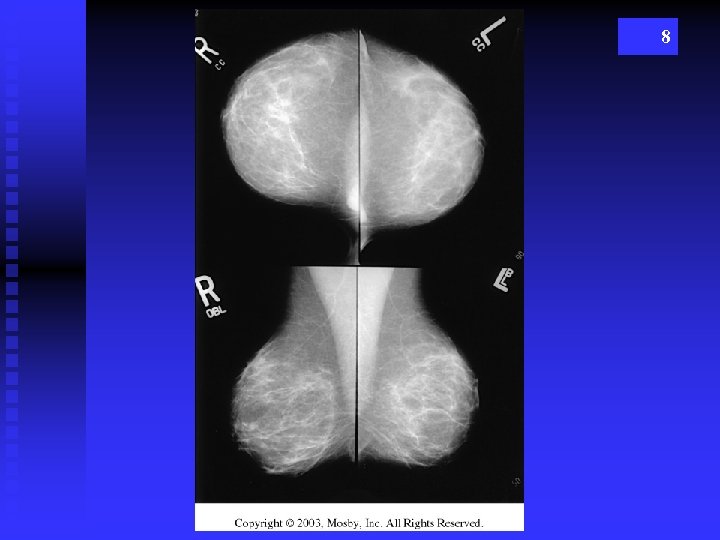

POSITIONING Routine Images aka “screening mammo” (not screaming) n. CC - cranio caudad n. MLO – mediolateral oblique 6

8